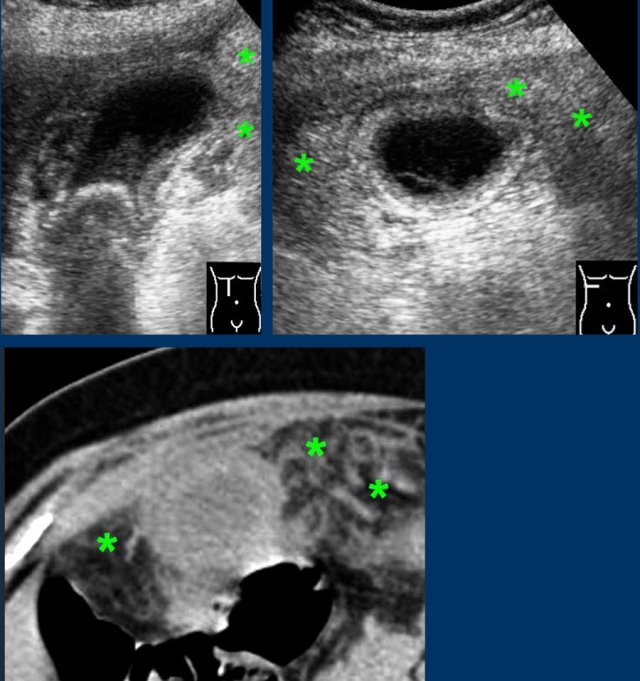

Advanced cholecystitis with inflamed fat ( asterisks) around the gallbladder fundus.

This represents the omentum, migrating towards the gallbladder in order to wall-off a possible perforation.

The images show a longstanding acute cholecystitis.

Note the large area of inflamed and indurated fat (asterisks) and the relatively small, somewhat compressible gallbladder.

This reflects a lumen filled with pus where the diseased mucosa is not capable of producing mucus under pressure anymore.

Drainage revealed pus.